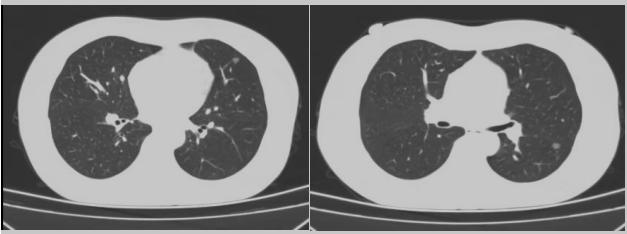

病例二:42歲的范女士,半年前體檢時發(fā)現雙側多發(fā)肺結節(jié),平時沒有什么不適。四個月后再次復查胸部CT,左上肺及下肺多發(fā)的磨玻璃結節(jié),其中下葉9mm的結節(jié)定為高危病灶??吹浇Y果范女士坐不住了,多方打聽慕名找到了市二院院長王瑾,經“肺結節(jié)MDT”團隊會診后,決定手術治療。入院后,胸外科副主任醫(yī)師薛飛詳細與范女士溝通,并利用Mimics做好了術前肺部三維重建手術規(guī)劃,打消了范女士心中的顧慮。經過前期充分準備后,歷經1小時30分,完成“胸腔鏡下左肺上葉舌段楔切及左肺下葉背段切除術”,術后病理檢查結果確診為左肺微浸潤性腺癌。在胸外科團隊的悉心照顧下,患者術后恢復良好,一周后順利出院。